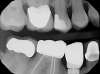

In addition to ensuring a laboratory is certified, it is important to make sure that all the parts from the implant company are authentic. This can be determined by asking to see the packaging for verification. Figure 3 shows a part on tooth No. 29 that is definitely not authentic. This piece may have been cheaper because it was not of verifiable quality. The dentist must ensure the quality of the products chosen. CAD/CAM has significantly altered the dental industry's approach to restorative treatment.15 The market and availability of products have increased, but consequently, the importance of FDA regulation has increased.

Fig 3. Inauthentic part on tooth No. 29.

Figure 3